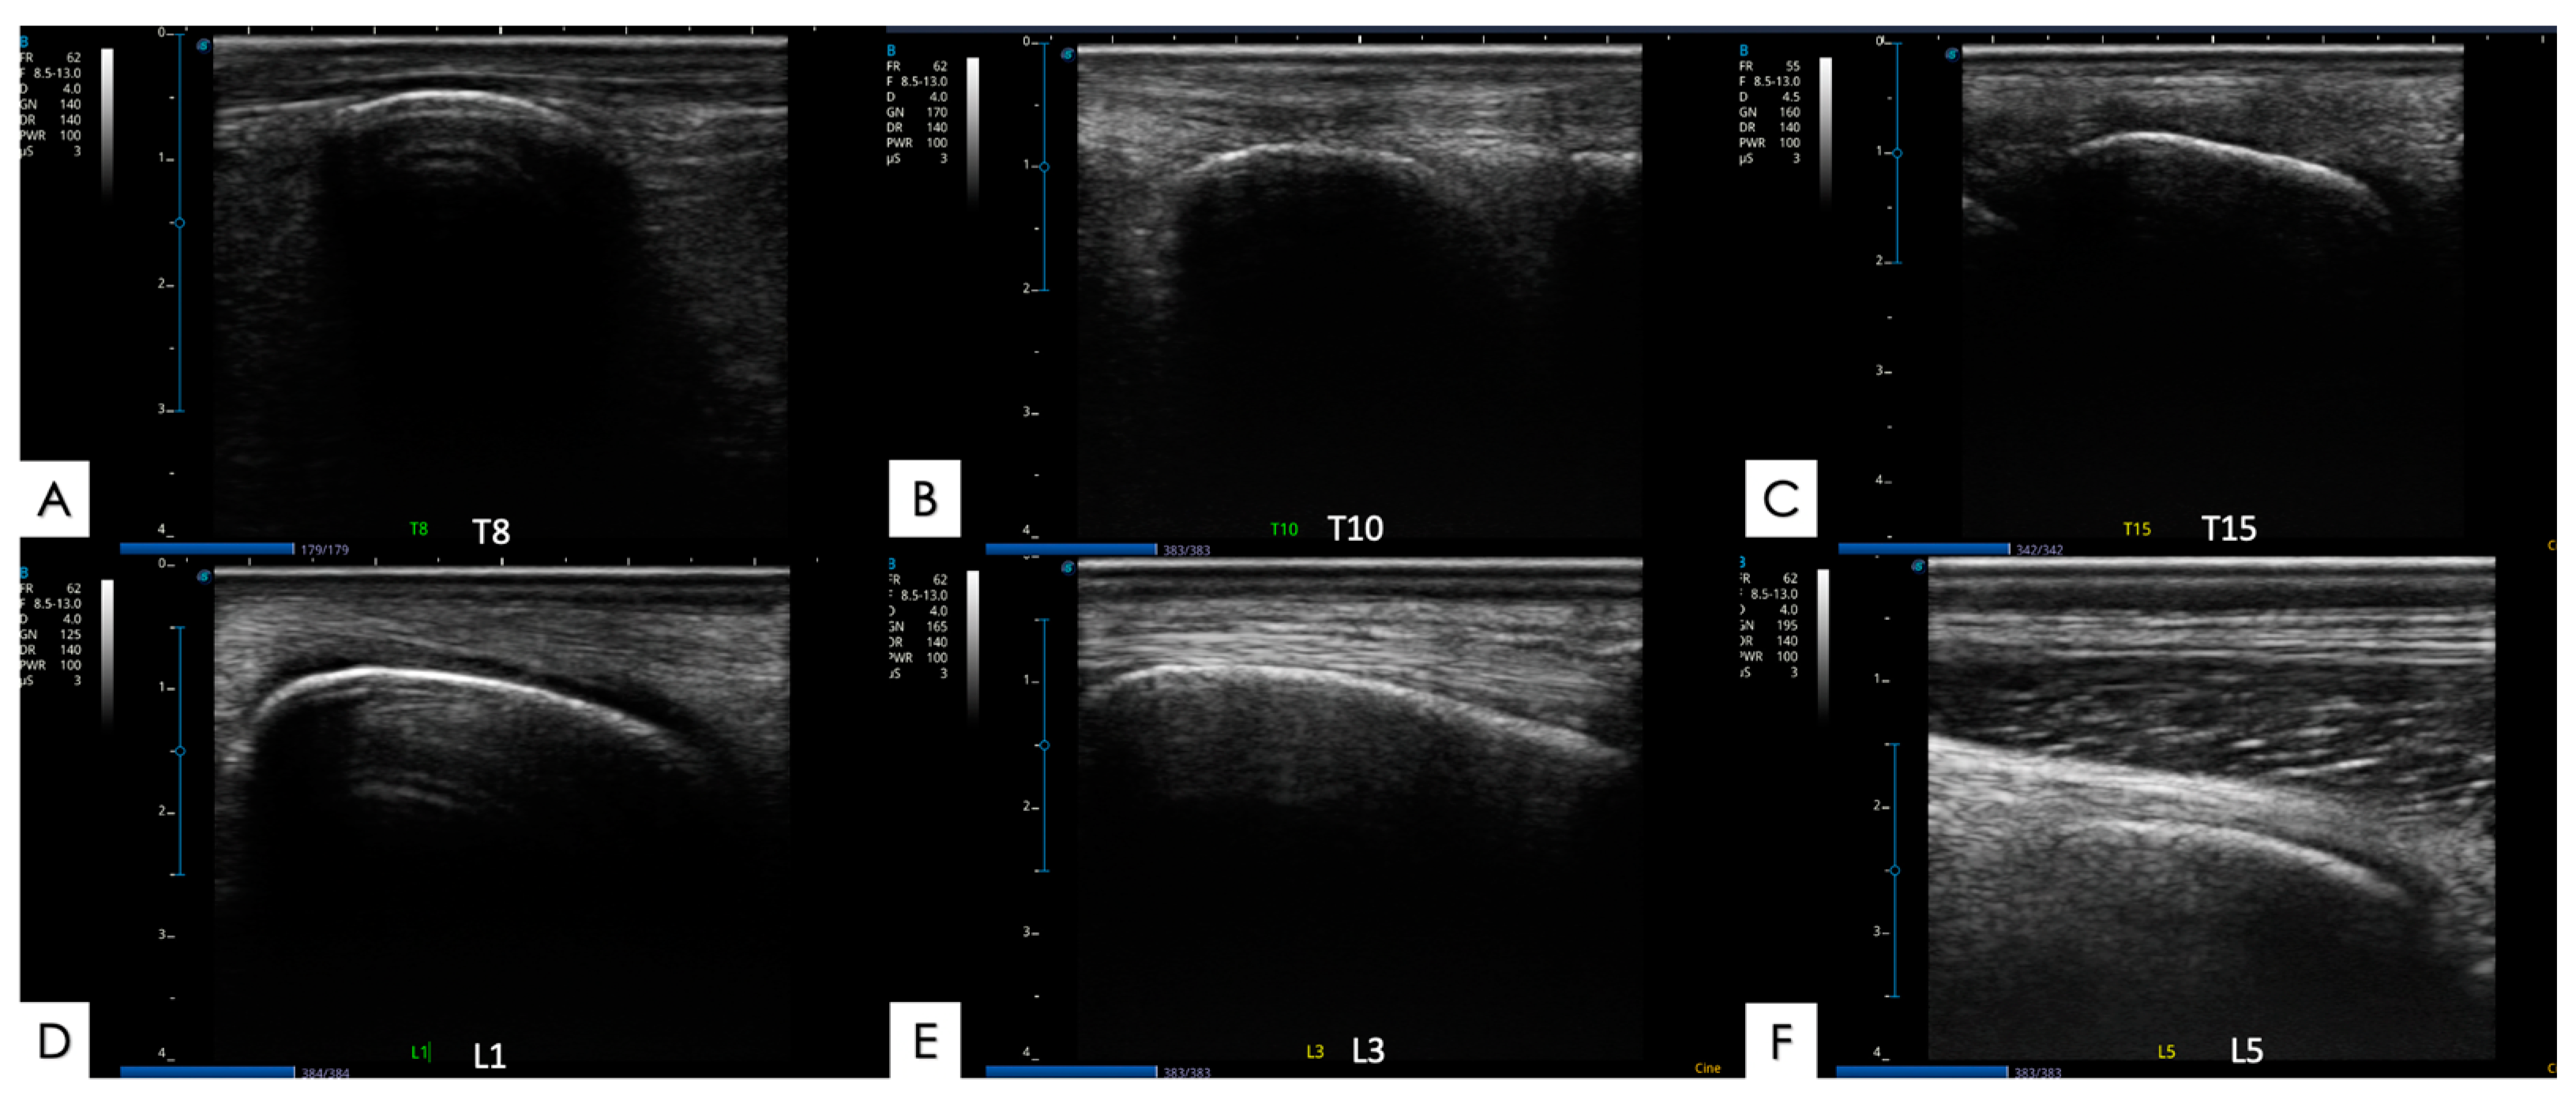

2.5.2. Spinous Processes and Supraspinous Ligament